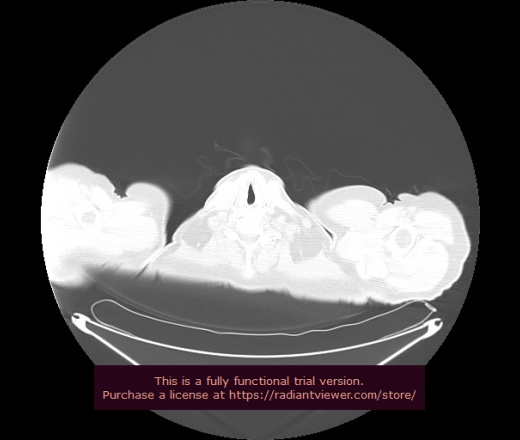

Уважаемые коллеги, если имеется интерес, сможете ли Вы спрогнозировать дальнейшее +-одинаковое течение процесса у 4 данных разных пациентов? Зацепиться где-то можно очень просто, где-то нельзя.